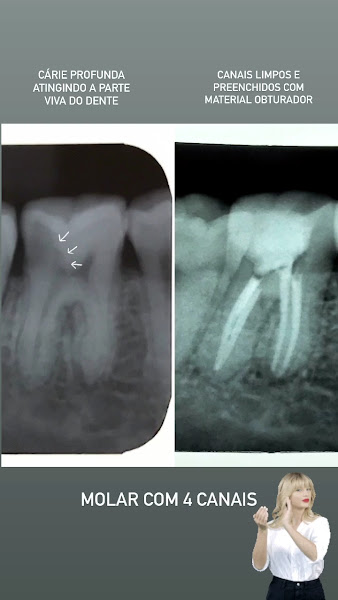

Dra Thaís é maravilhosa! Fez meu retratamento de canal de forma muito eficaz, não senti dor, nem incômodos e logo vi o resultado em um dente que estava bem inflamado. Além de ser super atenciosa e explicar tudo com muita paciência.